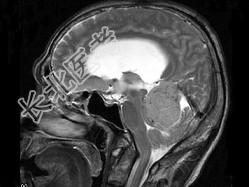

- 单项选择题男,61岁, 头晕头痛伴行走不稳1月余,根据所提供图像, 最可能的诊断是 ( )

A、胶质瘤

B、髓母细胞瘤

C、(天幕切迹缘)脑膜瘤

D、转移瘤

E、淋巴瘤